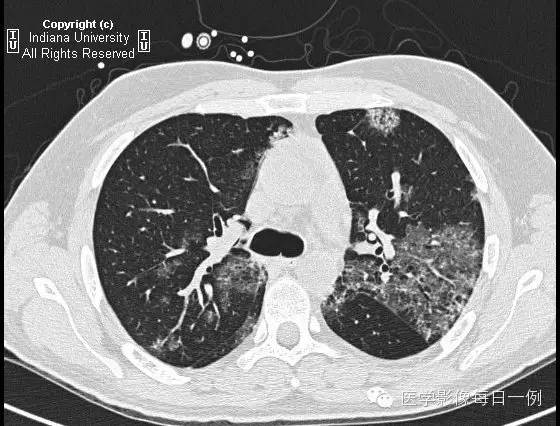

胸部CT示弥漫性肺泡透光度减低,主要位于右肺下叶和左肺上叶,呈铺路石样改变。胸膜无渗出。

【鉴别诊断】(铺路石征)

肺泡性出血

【诊断】Alveolar hemorrhage